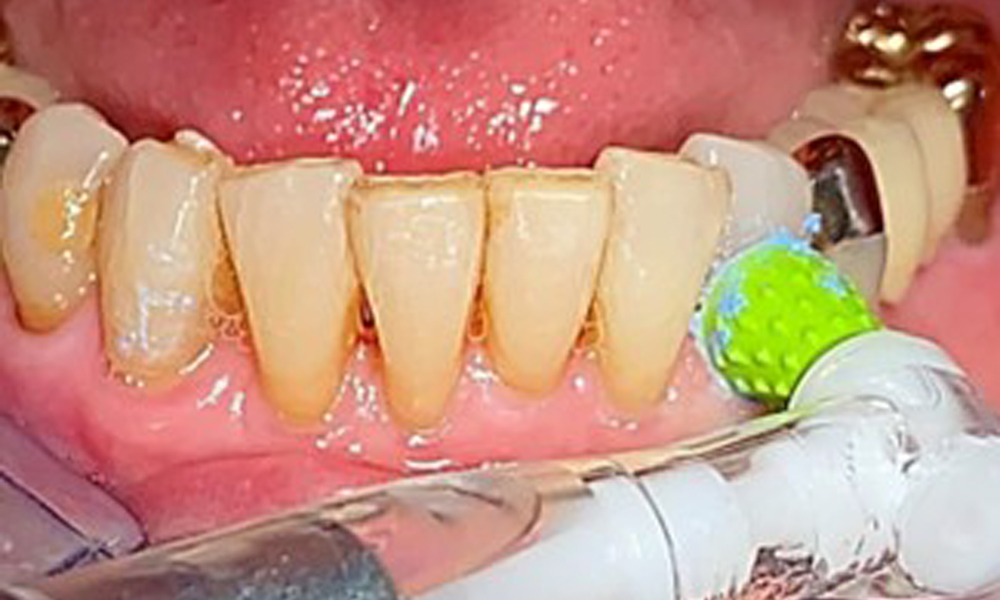

The patient brushes her teeth and implants three times a day with a manual toothbrush and single-tuft brush. She also uses interdental brushes once a day in the evening. She also cleans her prosthesis after every meal.

A single-tufted brush is specifically recommended for the telescopic prostheses (Fig. 8) and the patient should be advised on the appropriate interdental brush size (Fig. 9). The patient has been implementing these recommendations for intraoral hygiene at home for many years and was encouraged to continue during the professional preventive dental appointment.

An air polishing system should be used with low-abrasive powder to remove biofilm from the restoration margins, interdental areas and implant surfaces (Fig. 12). Selective polishing (Fig. 13) should be used to smooth any less sensitive areas, as this decreases bacterial reattachment (9).